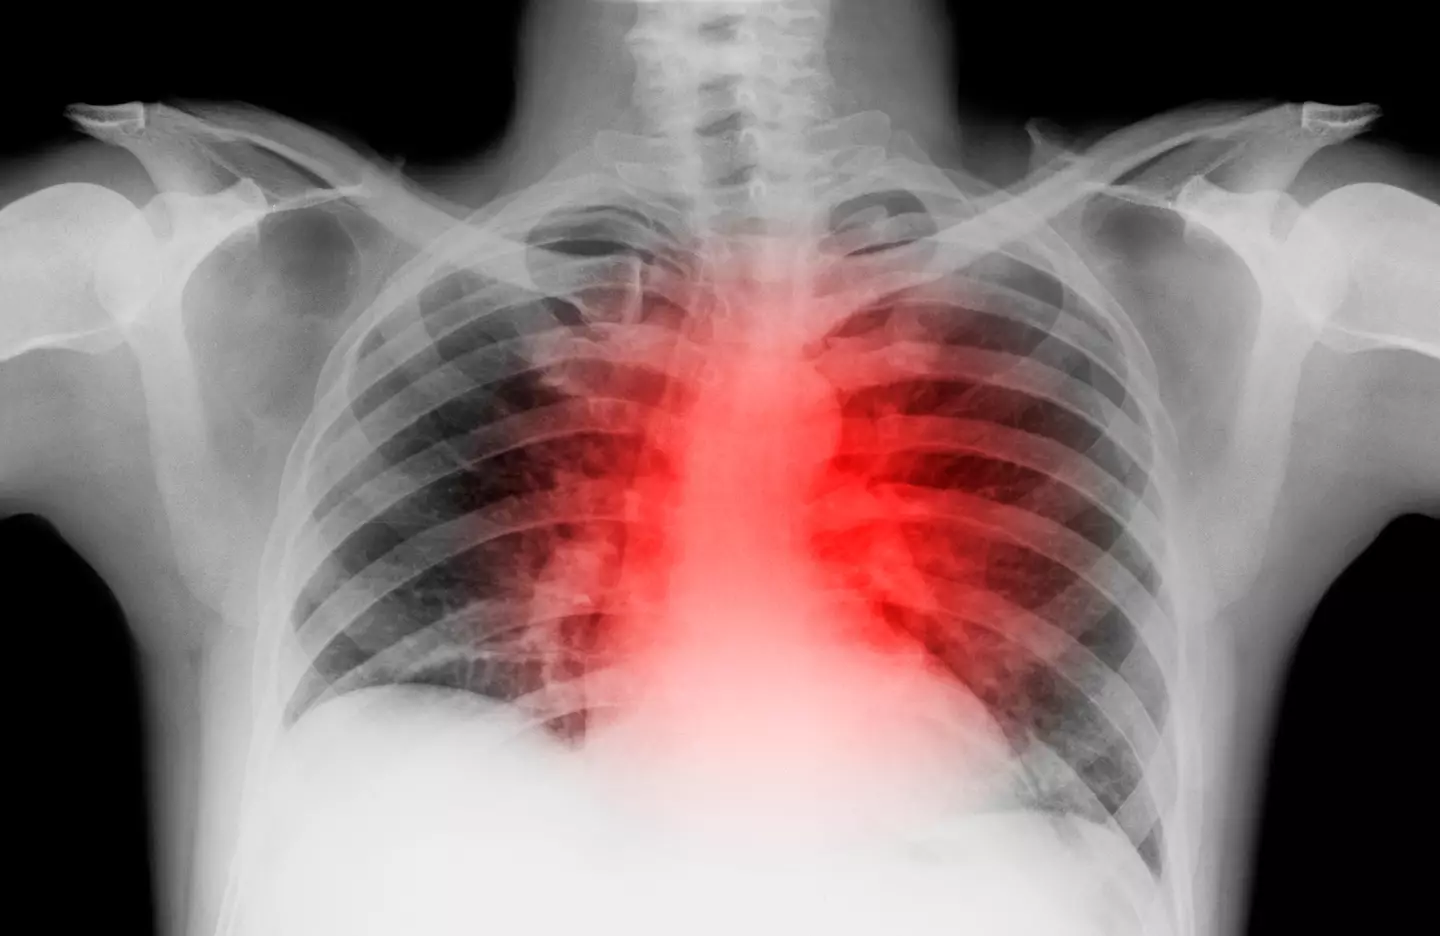

In more serious cases, it can lead to kidney or liver problems, heart attacks, or even strokes.